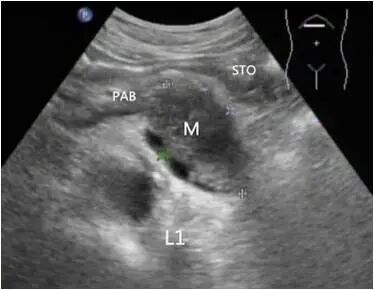

胰体尾部癌

第二种表现为胰腺内肿物不规则或有分叶状的团块回声,肿块边界不清,轮廓不整,向周围组织呈蟹足样或锯齿样浸润。

第三种表现为较小的肿块,内部大多数为均匀低回声,后方声衰减不明显;较大肿瘤呈混合回声,后方回声衰减,也可以看到坏死液化的无回声区。